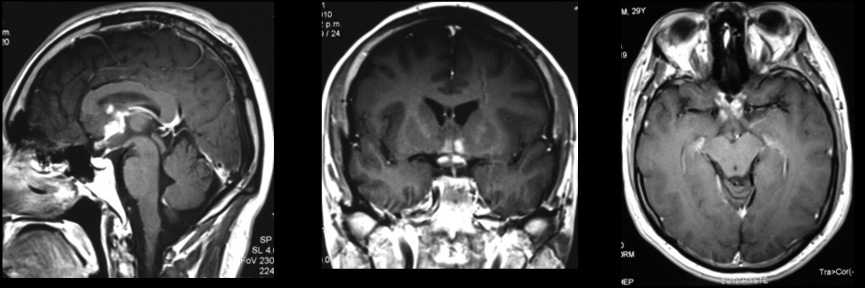

En la figura 6, que muestra una RM en TW-1 con gadolinio en corte sagital, coronal y axial del cerebro, se observan múltiples pequeños focos captadores conglomerados en región hipotalámica quiasmática y porción prequiasmática de nervios ópticos, en un varón de 29 años con disminución progresiva de la visión y hemianopsia bitemporal. Corresponde al primer caso de neurosarcoidosis diagnosticado por RM en el país, comprobado histológicamente (32).